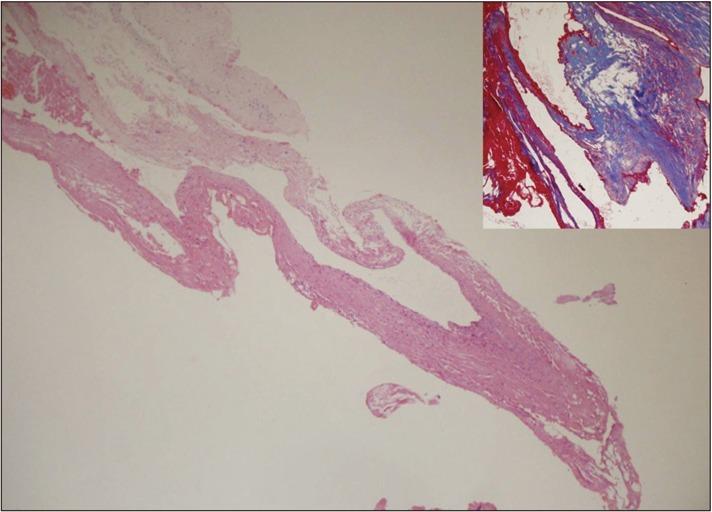

Spinal epidural arteriovenous hemangioma mimicking lumbar disc herniation.

A spinal epidural hemangioma is rare. In this case, a 51 year-old female patient had low back pain and right thigh numbness. She was initially misdiagnosed as having a ruptured disc with possible sequestration of granulation tissue formation due to the limited number of spinal epidural hemangiomas and little-known radiological findings. Because there are no effective diagnostic tools to verify the hemangioma, more effort should be put into preoperative imaging tests to avoid misdiagnosis and poor decisions).